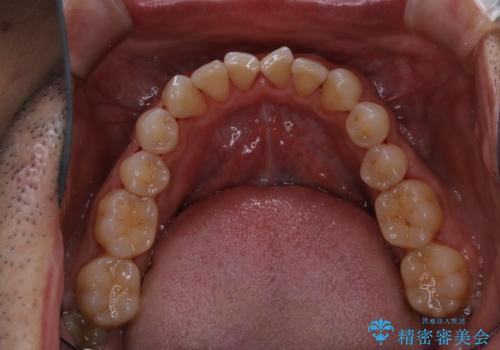

終了時

40年ぶりの来院との事で全体的に、古くからの歯垢・歯石が硬く多く付着していたため、自費クリーニング(PMTC)60分1万円+TAXコースを行いました。